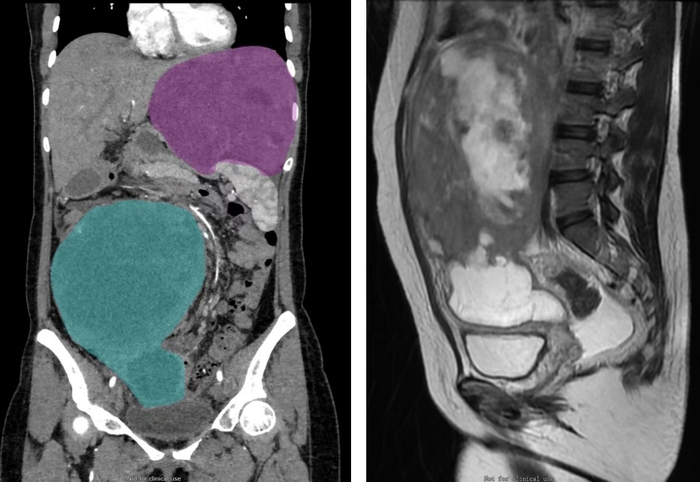

手术主刀医生、一妇婴院长王育介绍,此次接受手术的患者,其盆腔肿瘤直径已达20厘米,同时还有一个直径16厘米的上腹部肿瘤病灶,如延误救治,后果难以想象。目前,患者术后生命体征平稳,在医务人员的精心照顾下正处于恢复中。

次日,焦虑万分的晓晨抱着最后一丝希望,前往一妇婴妇科肿瘤科求助。磁共振检查证实了她的病情很严重:肿瘤生长速度极快,此时直径已达20厘米。子宫平滑肌肉瘤是常见的妇科恶性肿瘤之一,恶性程度较高、术后极易复发、肿瘤生长速度快,如不及时治疗,病情会迅速恶化,患者将失去后续治疗的机会。通过手术完全切除肿瘤并进行辅助化疗,可以为患者带来最好的预后。

而进一步的检查发现,晓晨的病情远比想象中更严重——这个盆腔肿瘤几乎占据了其盆腔及腹腔的所有空间,压迫了右侧输尿管,右侧肾几乎完全失去功能。而除了盆腔20厘米的肿瘤外,左侧上腹竟然还有一个16厘米的病灶,盘踞在肝、脾、胃之间,并压迫左侧胸腔,血供非常丰富。由于病情严重,肿块压迫了胃和大部分肠管,才让她感觉胸闷、腹胀,无法正常饮食。